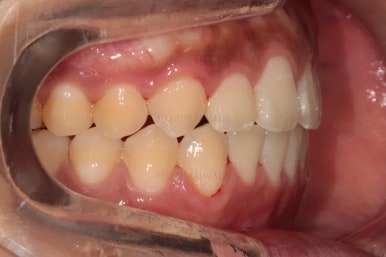

이 시점의 얼굴 모습인데요.

가지런한 치열의 느낌 좋고요.

옆라인도 비발치라고 입이 많이 나온 느낌은 아니죠.

현 시점에서의 옆모습 처음과 비교해 볼게요.

큰 차이 없죠?

대신 약간 나왔다면 나왔다고 느낄 수 있을 정도이긴 합니다.